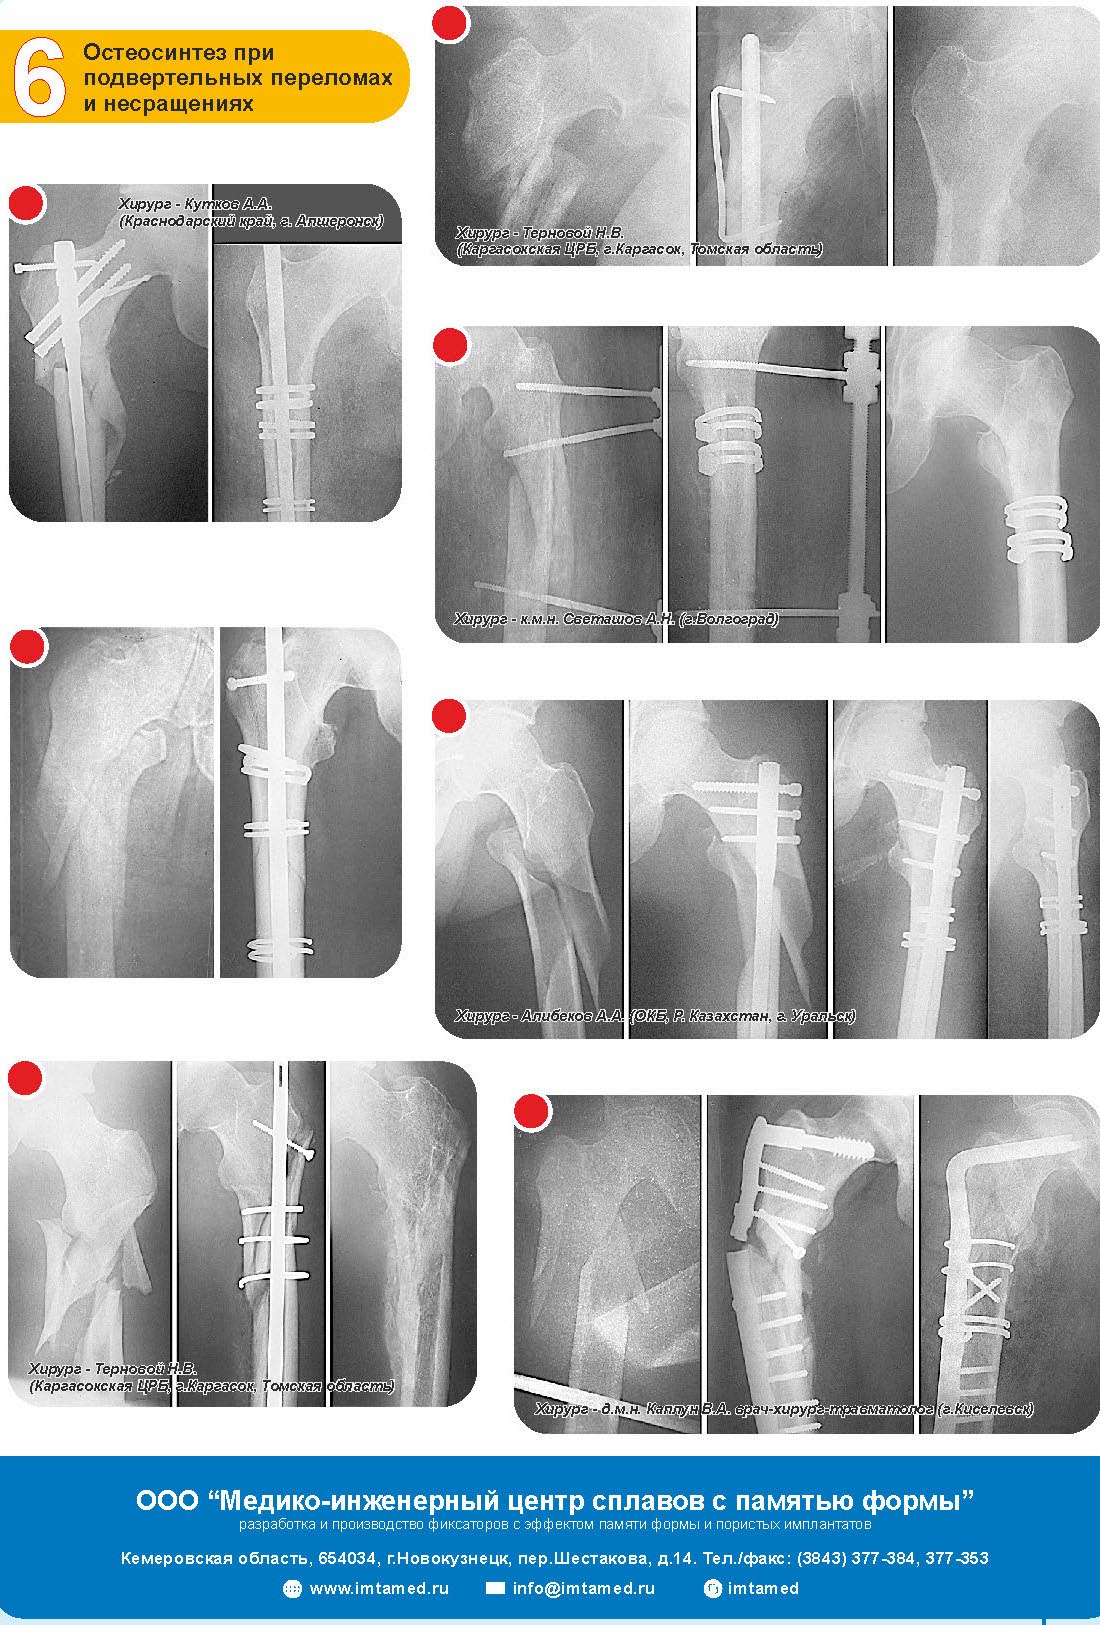

Imtamed 26 Ноябрь 2014, 10:43

Способы лечения